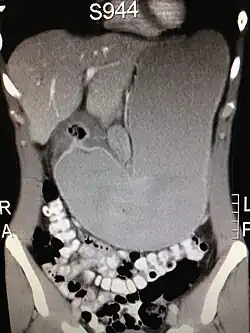

Magenausgangsstenose